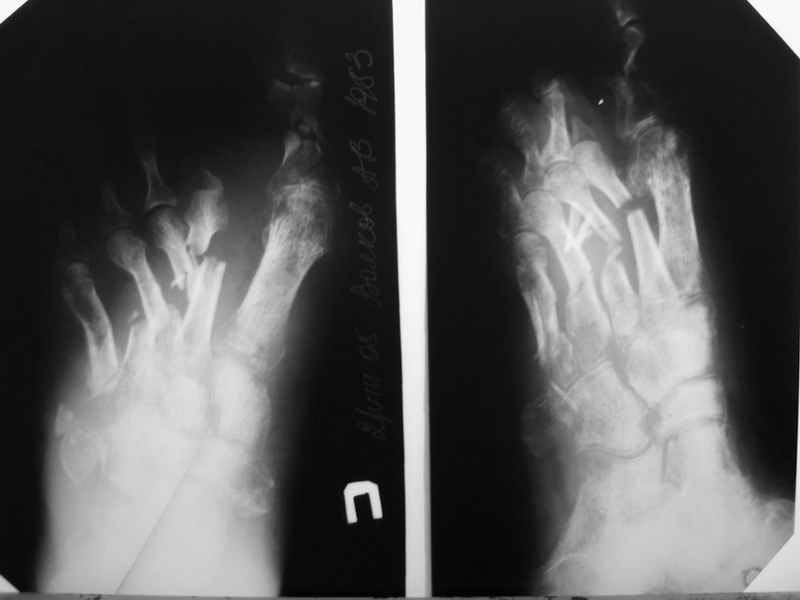

В продолжение темы конкретного больного. К сожалению, после достаточно длительной ходьбы несколько дней назад, появились классические признаки воспаления. Сегодня выполнил некрэктомию-дистальный отломок 2 плюсневой кости с остатком фрагмента основной фаланги- буквально плавали в гное. Рану тампонировал с левосином. Компенсации кровооброщения не наступило?

P.S. Перед операцией взял посев и на чувствительность, но ответ(в нашей лаборатории) скорее всего предсказуем-Staph aures. Посмотрим на чувствительность.

Здравствуйте Алексей, сожалею о продолжении воспалительного процесса, да видать спицевой остемиелит лечить придется долго. После купирования гнойного процесса через Департамент здравоохранения можно положить больного к нам в клинику. ( вы пишете бумагу в департамент, что мол больному показано лечение в ГКБ 64 и он сам или его родные получают такой красный талон на госпитализацию)

но я вот о чем подумываю, не пора ли подумать об ампутации? остемиелит можно лечит долго, любые железки будут выгнаиваться...

если есть возможность пришлите плз фотографии последних снимков и вида стопы

Здравствуйте, Тимур Вячеславович. Спасибо за живой интерес к проблеме: этапы к Вам понял. Насчет ампутации, я думаю, что больной еще не созрел, наоборот- полон оптимизма. Вот свежие рентгенограммы и стопа на 5 день после операции. Появились грануляции, но рана глубокая- 2-2,5 см. Хотелось бы узнать о Вашей тактике на ближайший период, если это возможно. С уважением, Алексей